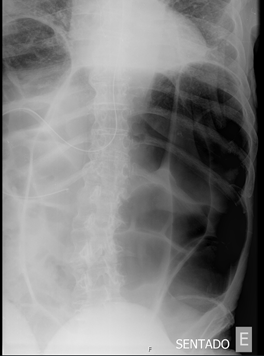

Figure 1 Plain abdominal radiography showing a markedly distended loop of bowel (“coffee bean sign”).

Elderly ill patients present unique challenges in the anamnesis, physical examination and to determine expectations for rehabilitation and meaningful recovery, being constipation a frequent geriatric syndrome.1,2 Sigmoid volvulus is characterized by abdominal distention and pain in the setting of constipation, and the diagnosis can be made with plain abdominal radiography. Common radiographic findings include absence of rectal gas, distention of the sigmoid colon in a coffee bean–like configuration, and a sigmoid colon transition point.1,2

In this case, a plain abdominal radiograph showed a coffee bean-like sign, suggestive for colonic volvulus. A computed tomography scan confirmed a huge colonic volvulus. Based on the patient’s history and surgical risks of an aggressive treatment in a frail patient, it was decided to perform an emergency colonoscopy for decompression. While without such comorbidities, immediate laparotomy would be considered, that would bring additional burden and discomfort without long-term benefit nor probable return to baseline.1,3